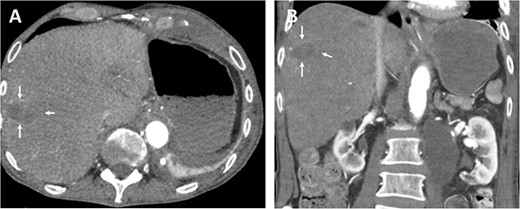

The oral antibiotics were administered and continued for another 10 days, and the patient was discharged on the 12th postoperative day in good general condition, fully mobilized, free of fever and infections. Follow-up CT showed a stable hepatic lesion (Fig. 4).

Follow-up (46 months after liver infarction) axial (A) and coronal (B) CT angiographic images demonstrate a stable hepatic infarction lesion 33 × 18 × 20 mm (arrows).